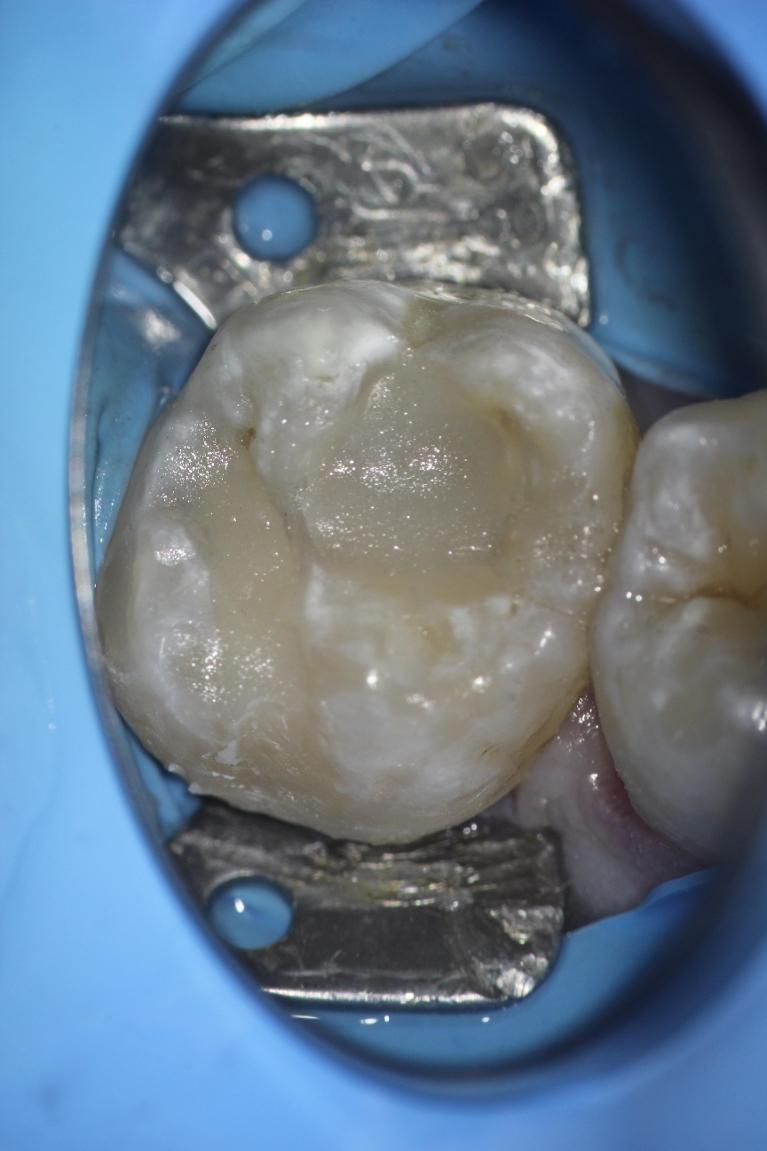

Welcome to our smile gallery, where you can browse photos of some of our best work. We hope that you find inspiration here for what is possible for your own smile. If you are considering cosmetic dentistry or you need help getting on track with your oral health, we look forward to hearing from you.

In the meantime, enjoy our before-and-after photos. We look forward to providing you with the same exceptional results.